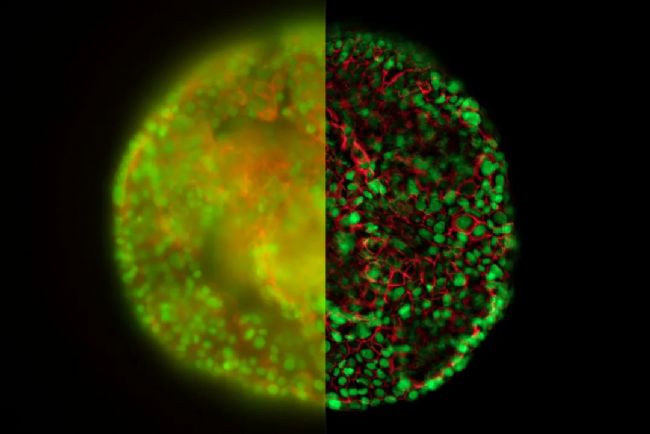

胰島 - THUNDER技術-3D細胞培養

對離體人類胰島進行 EDoF 重建,以實驗檢測單個人類胰島細胞中促炎細胞因子 IL-17 的表達。圖像具有以下標記:胰島素(AF488;綠色)、胰高血糖素(AF555;紅色)和 IL-17(AF647;品紅色)以及 Hoechst(細胞核;藍色)。圖片由美國加利福尼亞州拉霍亞免疫學研究所 Matthias Von Herrath 實驗室提供